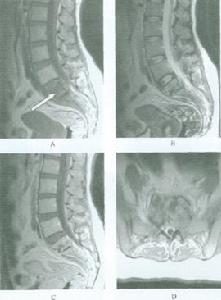

單純脊柱結核方先之1956年對施行結核病灶清除療法的941例進行分析總結,寫成《骨關節結核病灶清除療法臨床報告》專著,又在雜誌上發表多篇論文。此種方法很快在全國推廣普及,不少縣醫院已能施行這種手術。中西醫結合治療骨折 他接受過西醫教育,對四肢骨折一直主張切開整復內固定,對關節內骨折更是如此。開始他對中國傳統正骨科治療骨折知之甚少。當中西醫結合治療被提出後,開始他對此不理解或持保留態度。他虛心地觀看老中醫的手法復位及固定方法。當他看到不少骨折患者經中醫整復取得明顯療效時,逐漸轉變了看法,但他也不是簡單地模仿套用,而是從大量臨床實踐中分析研究,將其上升到理論高度。他既看到中醫正骨科有手法簡單、功能恢復快等優點,又看到復位不盡滿意、固定不夠可靠等不足之處,於是對此加以改進,形成一種獨特的中西醫結合療法。

惡性腫瘤方先之在骨科的各個分支常提出一些新的看法或在技術上作某些改進。他是中國首次介紹腰椎間盤突出手術的學者,早在1949年,他就在( 《中華醫學雜誌》英文版)發表了有關論文,他認為腰椎間盤突出的主要病理為纖維環破裂突出,導致腰神經根受壓,因此,本病應稱為腰椎間盤纖維環破裂症。